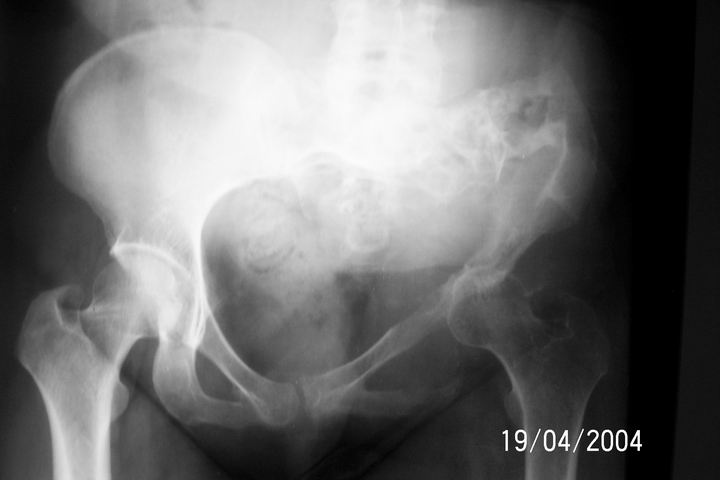

Chondrosarcoma

Dear All, I am attaching an x-ray of 33 - years- old female patient Biopsy report: Chondrosarcoma.

I would appreciate your inputs regarding this case. Regards